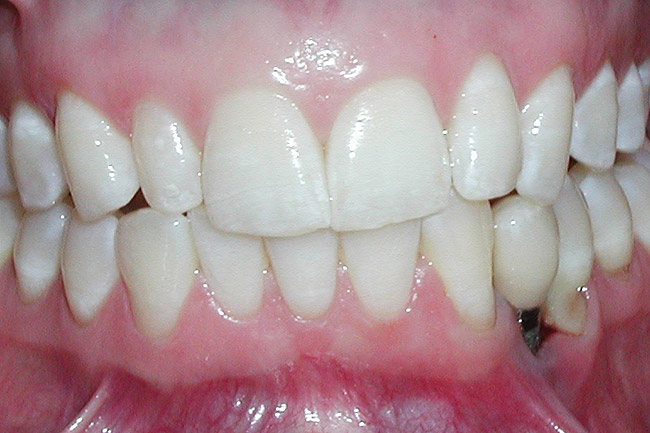

Figure 12  Right buccal view showing posterior occlusion established, canine guidance and proper space appropriation around peg lateral tooth No. 7, and intruded worn incisors.

Figure 12